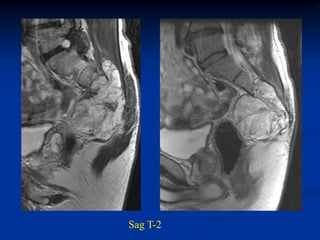

Case #220                 Sagittal T-1 MRI

74 year male with chordoma sacrum

Sagittal T-2 MRI